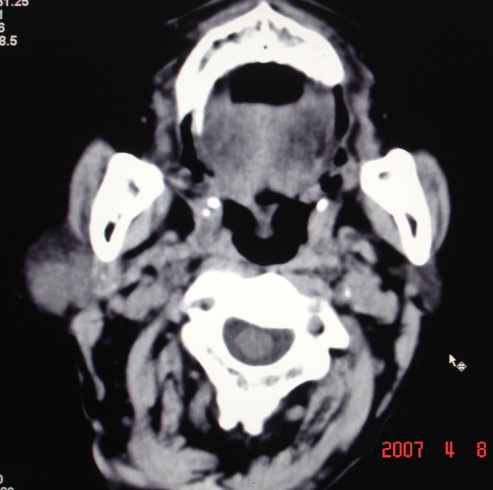

以下是引用zjzjr在2007-4-9 13:27:00的发言:[br]右侧腮腺深浅叶可见一混杂密度区,含有实性及囊性成.考虑右侧腮腺混合瘤,建议ct增强扫描。

以下是引用jiangjing在2007-4-9 15:09:00的发言:[br]考虑右侧腮腺肿瘤[混合瘤可能性大],其他待排[br]建议ct增强扫描。